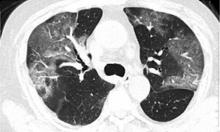

April 6, 2020 — Children and teenagers with COVID-19 showed distinctive clinical and computed tomography (CT) findings, according to a new study published today in Radiology: Cardiothoracic Imaging. Compared to adults, pediatric patients generally had milder clinical symptoms, fewer positive CTs, and less extensive involvement on imaging.